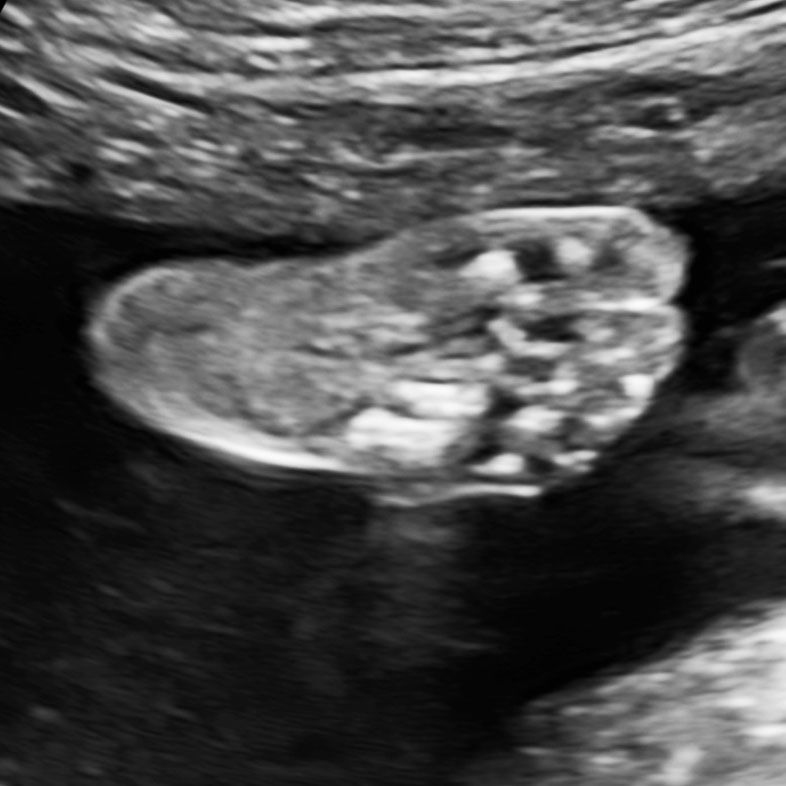

The Anomaly Scan involves a thorough examination of the fetal anatomy including a top-to-toe examination of the baby and its environment in the womb. We have the most comprehensive list of organs and structures that we examine, paying special attention to the fetal brain and heart.

- We perform meticulous top-to-toe examinations of the fetus and check more structures than any other institution,

We perform an advanced fetal heart examination for every baby we scan,

We have a comprehensive checklist, even your baby’s tiny feet